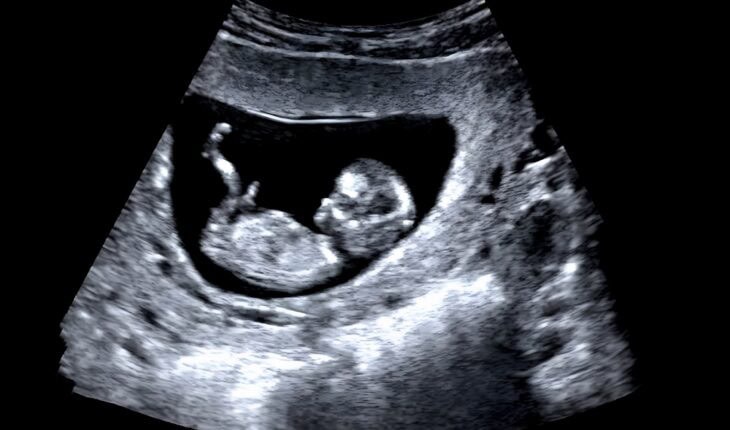

Despite CO being a well-recognised environmental toxin, there remains a fundamental lack of understanding of its impact on vascular health and disease. This project will build on previous CORT-funded work at Manchester Met and aims to uncover how CO exposure affects the developing cardiovascular system, with a particular focus on the unborn child.

Research has already shown that even low levels of CO exposure—around 8ppm—can interfere with heart formation in embryos, leading to congenital heart defects. Moreover, CO has been linked to vascular dysfunction and increased risks of heart disease, vascular dementia, and deep vein thrombosis later in life.

“CO exposure can have a huge impact on vulnerable groups, and in particular during pregnancy. The extent to which it can affect a foetus and its developing heart is still not fully understood. Dr Ridge’s project will build on Manchester Met’s previous work and investigate how CO exposure affects blood vessels and their functionality. We are pleased to support this important research and to once again collaborate with Dr Ridge and his colleagues at the University.”